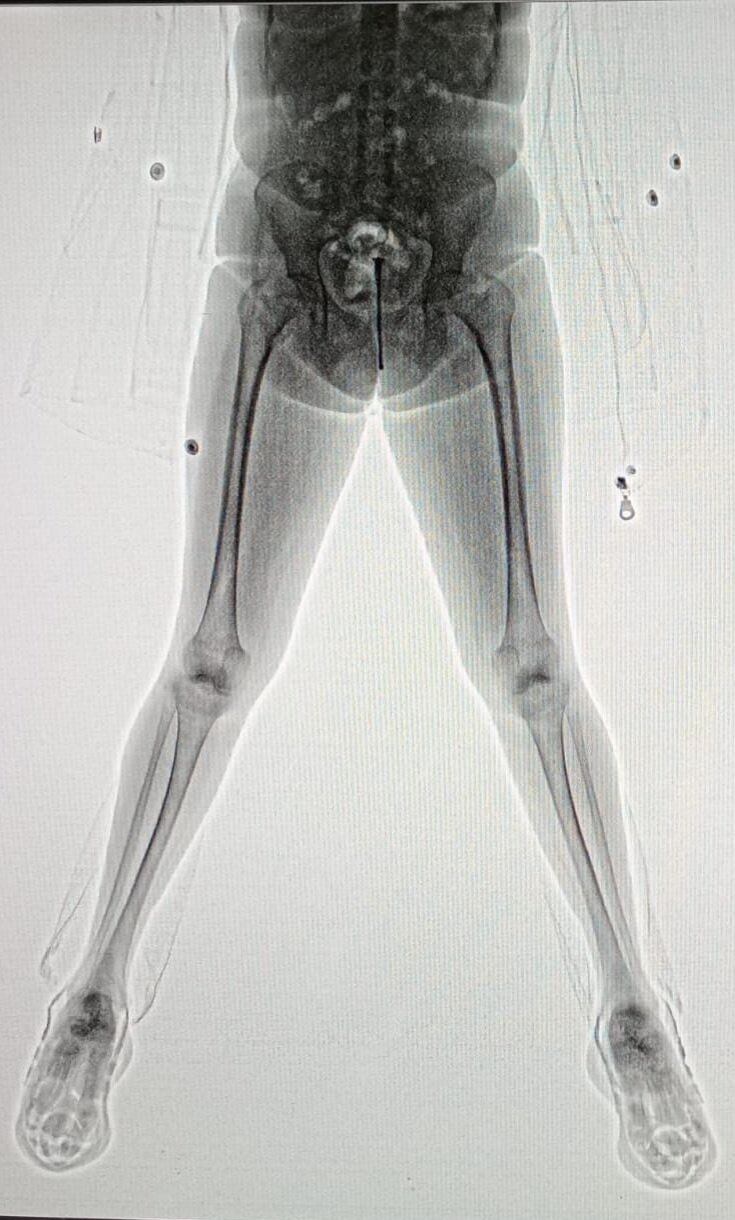

El hecho ocurrió en el marco de las visitas habituales al Establecimiento Penitenciario N° 5. El ingreso de la visitante al penal se produjo bajo las medidas de control reglamentarias, que incluyen el paso obligatorio por un body scanner.

De acuerdo con la información a la que pudo acceder el medio local ElDoceTV, durante la inspección, el personal del Servicio Penitenciario identificó anomalías en el calzado de la mujer, situación que motivó una revisión más exhaustiva.

Al retirar las zapatillas y examinarlas, los ofciailes encontraron 10 envoltorios de nylon, cada uno de ellos relleno con una sustancia de color blanco, compatible con clorhidrato de cocaína, motivo por el que se dio intervención inmediata a la Fuerza Policial Antinarcotráfico (FPA), que ahora tomó intervención en la investigación.